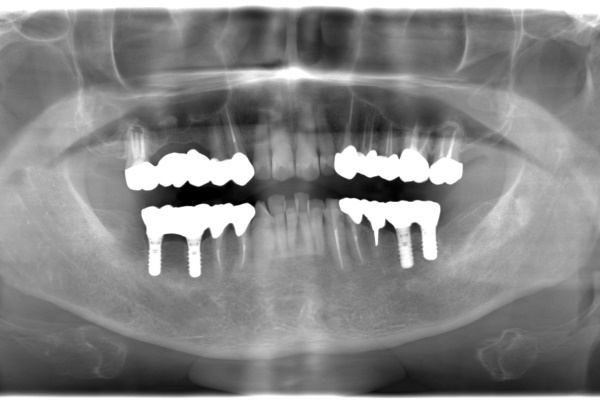

インプラント治療の治療例です。

主訴は「奥歯で噛めるようにしたい」というご希望でした。

下顎の奥歯にインプラント治療を行い、咬み合わせを回復しました。

- 治療方法 下顎の奥歯にインプラントを埋入し、咬合を再建